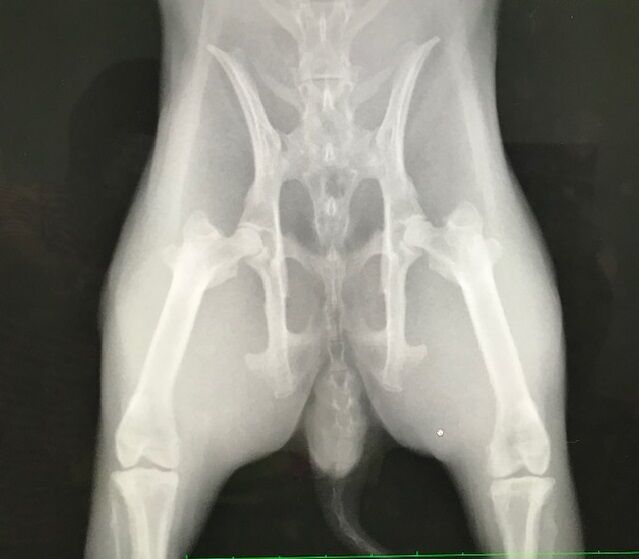

うちではダイちゃんの歯根膿瘍緩和にならんかなぁって。